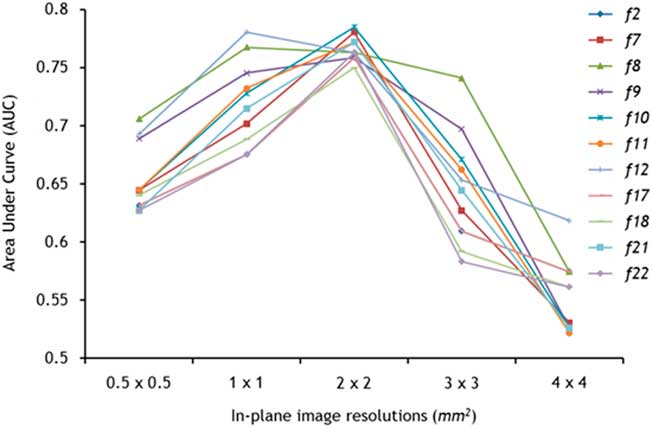

Texture features that were different between ALS patients and healthy controls after correcting for multiple comparisons were selected for ROC analysis to examine their diagnostic accuracy. Features f 2, f 7, f 8, f 9, f 10, f 11, f 12, f 17, f 18, f 21, and f 22 showed significant differences at 2×2 mm2 and were selected for further analysis. An AUC was calculated for each feature at all five resolutions.

Every feature improved in its performance (with increasing AUC), with decreasing image resolution from 0.5×0.5 mm2 to 1×1 mm2 to 2×2 mm2 (Figure 2). A peak in the AUCs was observed at 2×2 mm,2 after which the features’ AUCs declined with further reductions in resolution. The exceptions to this trend were features f 8 and f 12 that peaked at 1×1 mm2 and declined with decreasing resolution. The highest AUCs were achieved at 2×2 mm2 by features f 10 (0.785) and f 7 (0.781), both with a sensitivity and specificity of 100% and 58%, respectively. In addition, at 2×2 mm2 AUCs for all features were clustered around the mean AUC, whereas at other resolutions a wider spread of values was observed. Average AUCs of the texture features at each resolution are presented in Table 5.

Figure 2 The discriminatory ability of texture analysis was dependent on image resolution. Nine of 11 texture features followed a trend with superior classification (highest area under the curve) peaking at 2×2 mm2.